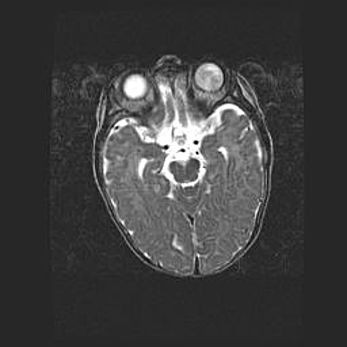

Мальформация Денди-Уокера. Киста задней черепной ямки.

Агенезия мозолистого тела.

Возраст: 2,5 месяца

Вес: 2420 г

Пол: женский

Окружность головы: 37 см

Срок гестации: 32 недели

Мальформация Денди—Уокера — редкий вид патологии ЦНС, представляющий собой врожденный порок развития каудального отдела ствола и червя мозжечка, ведущий к неполному раскрытию срединной (Мажанди) и латеральных (Лушка) апертур IV желудочка мозга. Для этогно синдрома характерна триада симптомов: гипотрофия червя мозжечка и/или полушарий мозжечка, кисты задней черепной ямки, гидроцефалия различной степени. В 70% случаев порок сочетается и с другими аномалиями головного мозга, в частности с агенезией мозолистого тела.